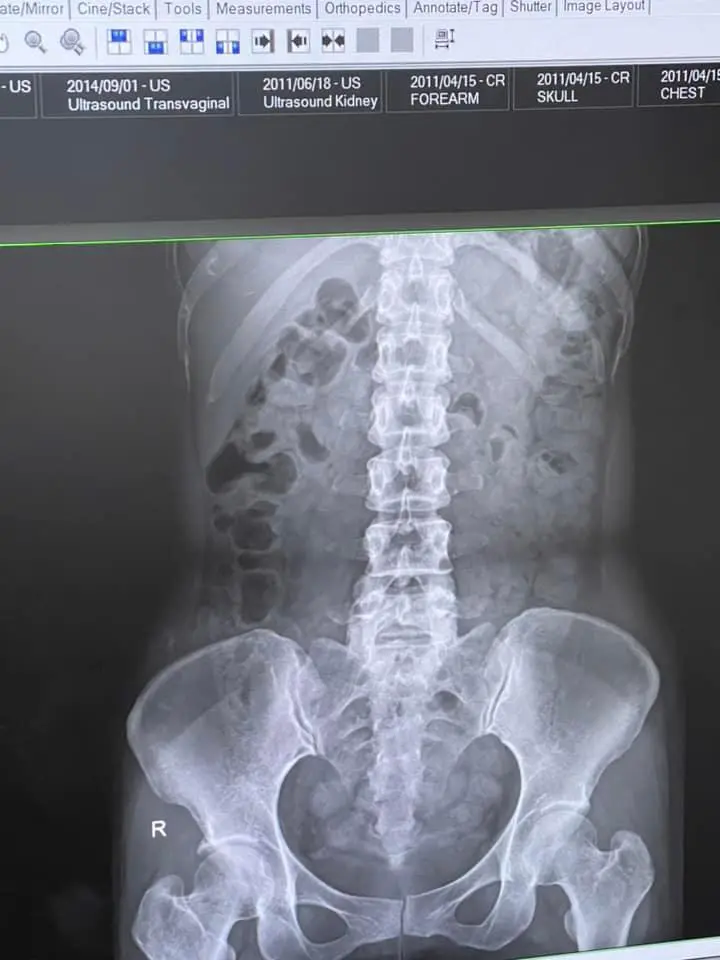

หลังจากเอ็กซเรย์เสร็จ หมอก็ได้แจ้งกับเธอว่า “คุณจมาพร มีอุจจาระอยู่เยอะมาก ๆ เลยครับ เต็มท้องเลย มันเลยทำให้เกิดลมจำนวนมาก แล้วก็เกิดอาการคลื่นไส้อาเจียน” โดยหมอยังบอกอีกว่า เวลาเราปวดอุจจาระ แล้วเราไม่ยอมไป จากที่จะต้องออก 10 มันจะออกแค่ 5 มันออกไม่หมด ทำให้มันคั่งค้างอยู่ในลำไส้จำนวนมาก นั้นเอง